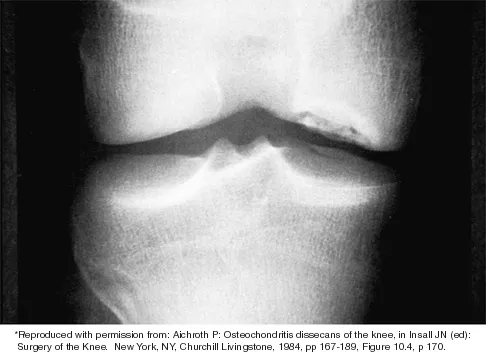

Which of the following primary prognostic factors best predicts the outcome of the knee lesion shown in Figure 22?

Explanation